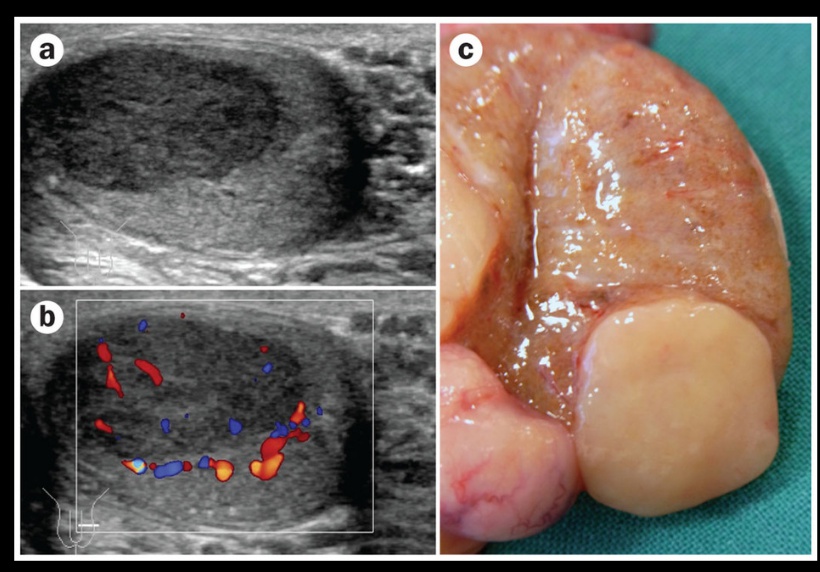

_The diagnosis of testicular cancer is often made with ultrasound, which reveals a hypoechoic intratesticular mass..

Seminoma

_The most common testicular tumor (40%) that originates in the germinal epithelium or the seminiferous tubules.,; resembles ovarian dysgerminoma.

Testicular ultrasound showing a hypoechoic intratesticular mass.

_On histology will reveal clear, polygonal germ cells with round nuclei and prominent nucleoli that are arranged into lobules and surrounded by septa. There is often a lymphocytic infiltrate and granulomas. Grossly these tumors appear as a bulky, gray tumor without hemorrhage or necrosis.,

_Most commonly present with painless testicular enlargement.,

_Highly radiosensitive and have an excellent prognosis with treatment. Later stage neoplasms often require surgical resection (orchidectomy)..